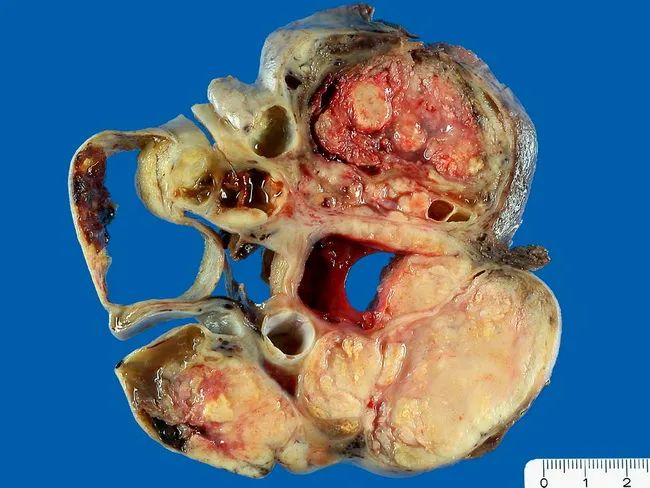

高级别浆液性癌high-grade serous carcinomas (HGSC)

(大体)常常双侧发生,切面呈囊实性或实性,常伴坏死,输卵管通常嵌在卵巢肿瘤内 (大体上常难以识别),通常有广泛的卵巢外受累(盆腔腹膜、肠管等脏器)